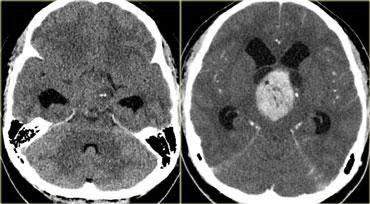

TRÁI: Di căn não. PHẢI: Nhiều u màng não và u thần kinh bao ở bệnh nhân U xơ thần kinh type II (Neurofibromatosis II)

Bệnh đa ổ

Nhiều khối u trong não thường gợi ý bệnh di căn (hình minh họa).

Các u não nguyên phát thường gặp ở một vùng duy nhất, nhưng một số u não như u lympho, u nguyên bào đa hình đa trung tâm (multicentric GBM) và u thần kinh đệm lan tỏa não (gliomatosis cerebri) có thể đa ổ.

Một số khối u có thể đa ổ do di căn gieo rắc: điều này có thể xảy ra trong u nguyên tủy bào (PNET-MB), u màng nội tủy (ependymoma), u nguyên bào đa hình (GBM) và u tế bào ít nhánh (oligodendroglioma).

U màng não và u thần kinh bao có thể xuất hiện nhiều ổ, đặc biệt trong bệnh u xơ thần kinh type II.